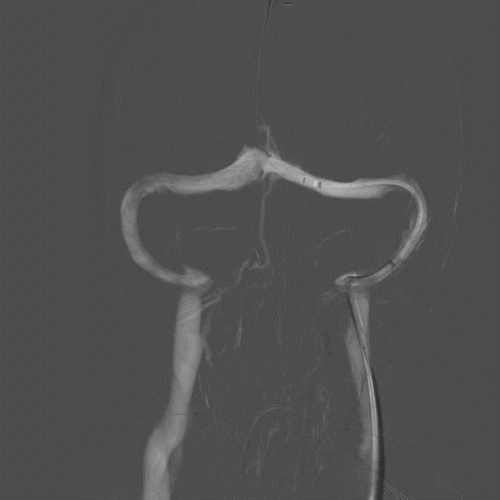

术前DSA:双侧横窦乙状窦交界处重度狭窄。

首先,建立右侧桡动脉通路,进行常规全脑血管造影,明确双侧横窦乙状窦交界区狭窄,排除动静脉瘘。再建立右侧股静脉通路,5F 125 造影导管与6F长鞘组成同轴系统,将长鞘置于右侧颈内静脉远心端。泥鳅导丝引导下将造影导管置于右侧横窦近窦汇处,通过造影导管行静脉窦测压,狭窄远端压力22mmHg,狭窄近端压力21mmHg,跨狭窄段压力差为1mmHg,故放弃右侧静脉窦支架植入术。

再利用同轴技术将6F 长鞘置于左侧颈内静脉远心端。尝试通过泥鳅导丝将造影导管置于左侧横窦失败,撤出造影导管,更换XT-27微导管,在Transend Floppy 300微导丝引导下顺利到达窦汇处。通过微导管进行静脉窦测压,狭窄远端压力26mmHg,狭窄近端压力18mmHg,跨狭窄段压力差为8mmHg,故决定行左侧静脉窦支架植入术。

撤除微导管,选用Precise 8*40mm支架,沿Floppy 300微导丝尝试将Precise支架越过狭窄段失败。撤出支架,沿Floppy 300微导丝将Tethys®中间导引导管顺利送达左侧横窦远心端。再利用特洛伊木马技术将Precise支架推送到位,回撤Tethys®中间导引导管,支架定位准确后成功于跨左侧横窦-乙状窦狭窄处释放。

在Tethys®中间导引导管下支架顺利通过左侧横窦乙状窦交界处

再次将XT-27微导管穿过支架送至横窦远心端,对支架远近端进行测压,支架远端压力22mmHg,近端21mmHg,压力差为1mmHg。复查造影提示左侧横窦狭窄显著改善,DynaCT未见颅内出血。遂结束手术。

术后即刻影像及患者术后情况:左侧横窦-乙状窦交界处狭窄显著改善,患者术后耳鸣较术前改善,视力无进一步加重,无头痛不适。

本例患者为一肥胖女性,以慢性进展性视力减退为突出临床表现,由于没有得到及时的诊断而引起了严重的双眼视力下降,右侧视神经甚至出现了神经萎缩。入院后通过血生化、腰穿、神经影像、DSA等检查,最终明确诊断为特发性颅高压合并静脉窦狭窄。通过对双侧静脉窦进行连续测压发现,左侧横窦-乙状窦交界处的跨狭窄压力差高达8mmHg,而右侧横窦-乙状窦交界处的跨狭窄压力差仅为2mmHg,于是我们对左侧横窦-乙状窦交界处的狭窄进行了介入治疗。

本例患者介入治疗中碰到的难点是支架无法在单纯的微导丝引导下越过左侧横窦-乙状窦的转角,考虑和系统的支撑性不足、支架的质地偏硬、横窦-乙状窦转角过大有关。我们及时调整手术方案,借助Tethys®中间导引导管,利用特洛伊木马技术,最终顺利地将Precise支架推送至目标位置,并成功释放支架,术后左侧横窦-乙状窦狭窄显著改善,跨狭窄压力差从术前的8mmHg,下降为术后的1mmHg。术中无出血、栓塞等并发症发生。术后3天复查腰穿提示颅内压显著下降,期待远期随访结果。